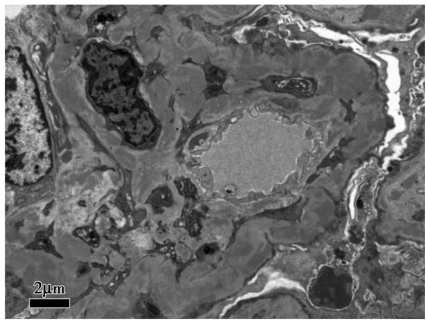

肾活检免疫荧光:IgG(+++),C3(+++),C1q(++),κ(+++),λ(+++),余阴性,系膜区、毛细血管壁颗粒样沉积(图1)。光镜下可见37个肾小球,肾小球系膜细胞和基质重度弥漫增生,广泛插入,肾小球基底膜弥漫不规则增厚,双轨及多轨征形成,系膜区、内皮下嗜复红蛋白沉积,其中2个小细胞性新月体形成;肾小管上皮细胞空泡及颗粒变性,多灶状萎缩;肾间质水肿,多灶状淋巴和单核细胞浸润伴纤维化;小动脉管壁增厚;符合膜增生性肾小球肾炎(图2)。电镜下肾小球系膜细胞和基质重度增生,广泛插入,内皮细胞增生及肿胀,基底膜弥漫不规则增厚,内皮下和系膜区可见电子致密物,上皮足突广泛融合;符合膜增生性肾小球肾炎(图3)。因怀疑HCV相关,进一步进行相关检测:免疫组化染色发现HCVNS3(nucleostemin 3)抗原沿毛细血管壁和系膜区颗粒样沉积,免疫电镜显示HCV-NS3主要位于电子致密物内。因此,该患者的病理诊断符合HCV相关的膜增生性肾小球肾炎。入院后予干扰素抗病毒,依那普利、美托洛尔、叶酸、维生素B12及对症利尿治疗,患者血肌酐渐上升至174μmol/L,伴血钾上升,停用依那普利;加用泼尼松、环磷酰胺治疗,患者尿蛋白渐降至<1g/d,SCr稳定在130μmol/L左右,目前随访1年,病情稳定。

图3 电镜在内皮下、系膜区可见电子致密物沉积(×8000)